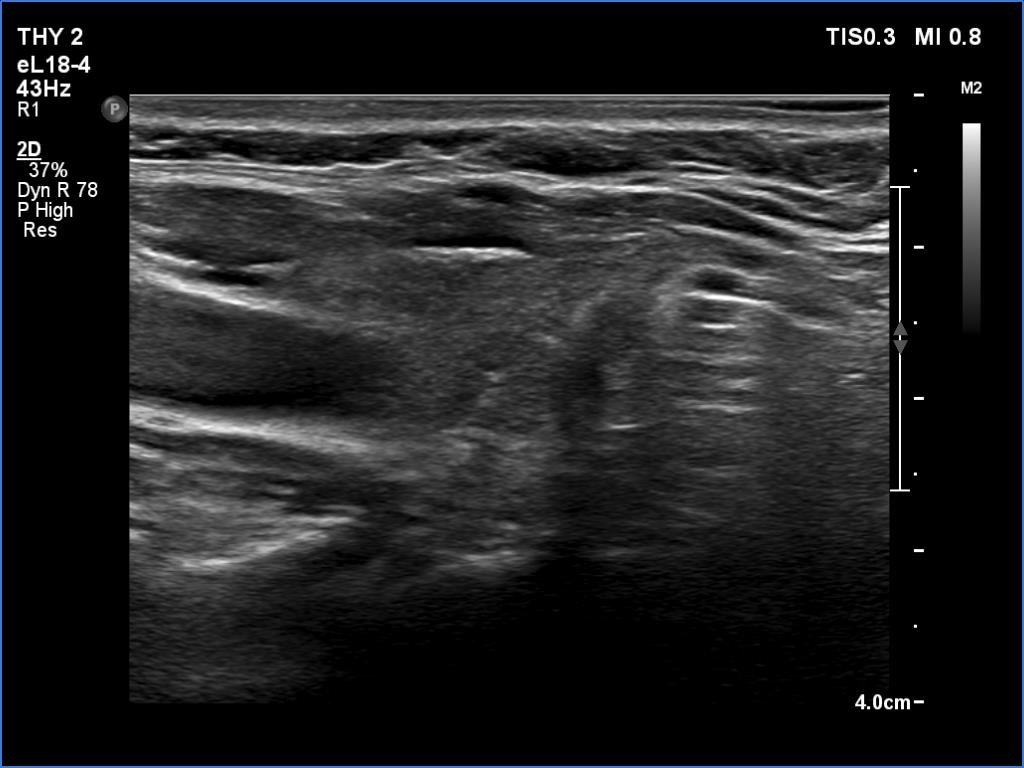

Subacute granulomatous thyroiditis - case 827

Follow-up examination five years later (ultrasonographic picture 2)

Right lobe, longitudinal scan.